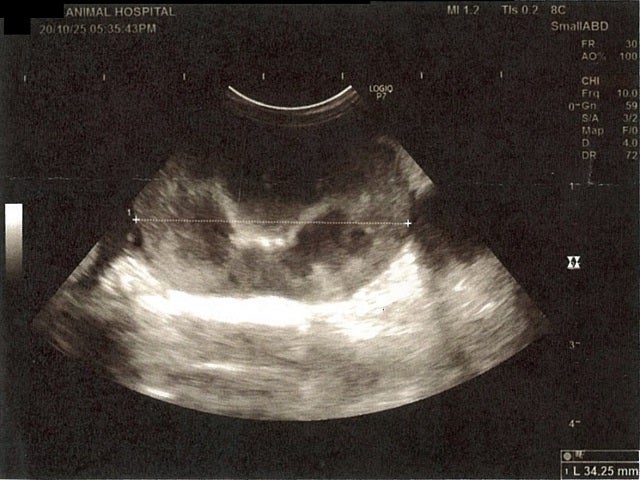

《心臓周りの胸部以外の全ての腹部で腹水がみられるとの診断です》

大網という部分で内臓を包む膜のようなものです。その周りに腹水が溜まっています。

膵臓周りに腹水が確認できるエコー写真

肝臓周りに腹水が確認できるエコー写真